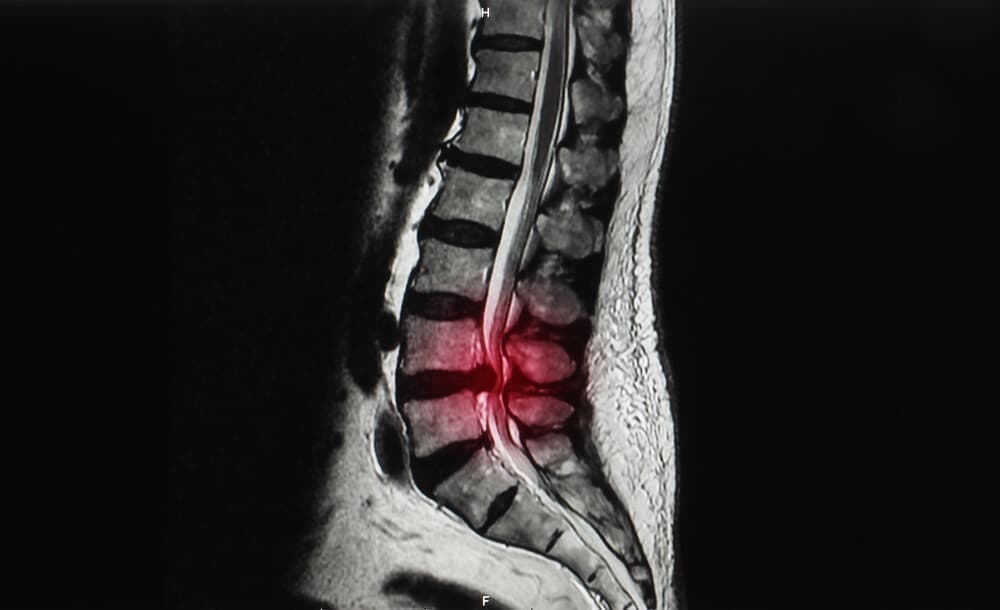

腰椎すべり症

背骨(脊柱)にある椎骨という骨にズレが生じている状態のことを腰椎すべり症と呼ばれています。

背骨(脊柱)は、椎骨がいくつも連結して形成されています。

すべりが生じることにより腰椎が安定せず、神経が通っている脊柱管が狭窄して神経に圧力を与えます。

その結果、腰から足にかけて痛みや違和感、しびれといった症状が現れるのです。